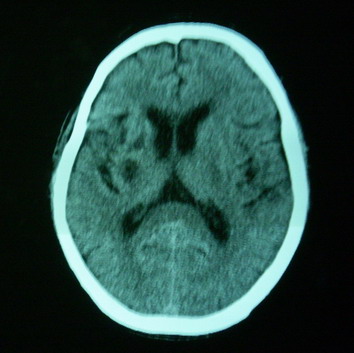

男,70岁,左侧肢体活动障碍口角向右侧歪斜2天,有高bp病史

pe:神情,能与之正常交流,吐字不清,180/90mmhg,双瞳孔无异常,左侧肢体肌力1级 b(+)

图中有个同心圆壮低密度影是ct伪影,见笑了。

1、右侧基底区及外囊区腔隙性脑梗塞。2、脑萎缩。

右基底节内囊前支区腔隙性脑梗塞,脑萎缩

支持右侧基底节区脑梗塞。

右侧基底区及外囊区腔隙性脑梗塞

右基底节区脑强隙 右基底节区低密度影密度太低 边界清 不会是2天的梗赛灶

2天左右的腔隙性脑梗死ct多难以发现 何况你的机器又差 很难显示 即使显示密度应该略低影

边缘模糊

支持腔梗。左内囊后肢亦有病灶